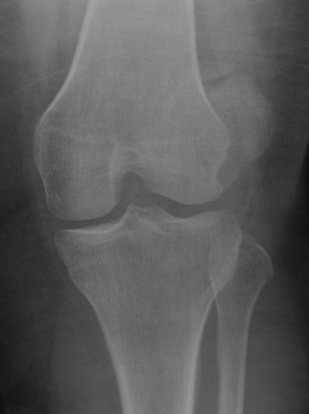

Xray

Look for osteochondral fractures

- AP xray: gutters

Loose body in lateral gutter